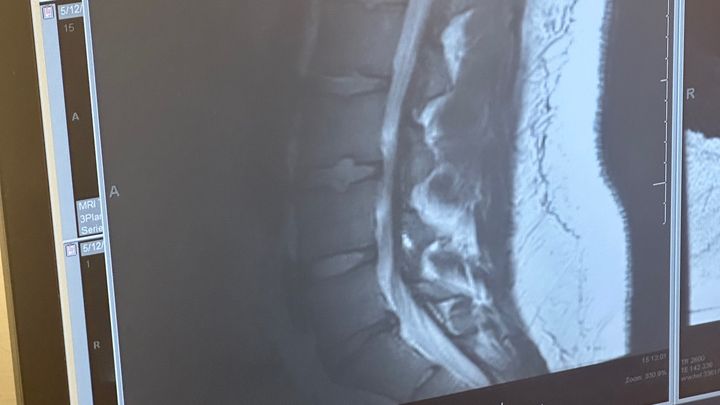

On Mother’s Day, I landed myself in the ER due to a flare-up of pain worse than I can recall. The ER determined the herniated disc has worsened, causing sciatica and damaging the nerves in my leg which has led to me losing a majority of feeling in my right leg and being unable to walk without a cane. After working with several doctors and getting lots of MRIs and tests done, the determination was made that the next course of action is surgical. This surgery should stop the rapidly increasing severity of pain and numbness in my back and legs and hopefully prevent the loss of sensation and feeling from becoming permanent.